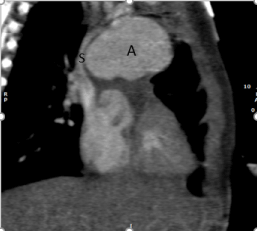

A child with history of tricuspid valve atresia, ventricular septal defect and interrupted aortic arch who underwent initial single ventricle palliation with Norwood procedure, modified Blalock Taussig (BT) shunt placement, and aortic arch repair at age of 11 days. His course was complicated by concerning finding for aneurysm on routine follow up echocardiogram. He had cardiac computed tomography (CT) imaging at age of 2 months. The cardiac CT showed giant aneurysm in the region of modified Blalock Taussig shunt that extends to anterior mediastinum (Figure 1-3). The patient was managed conservatively. At the time of the second palliative surgery, bidirectional Glenn procedure, at age of 7 months, the fibrosed tissue of pseudoaneurysm was resected. Subsequently the patient underwent fenestrated fontan procedure without any complication at age of 3 years and 9 months. He did well after his Fontan procedure.

Figure 1B. Cardiac CT reconstructed image in coronal view: A: aneurysm, S: superior vena cava